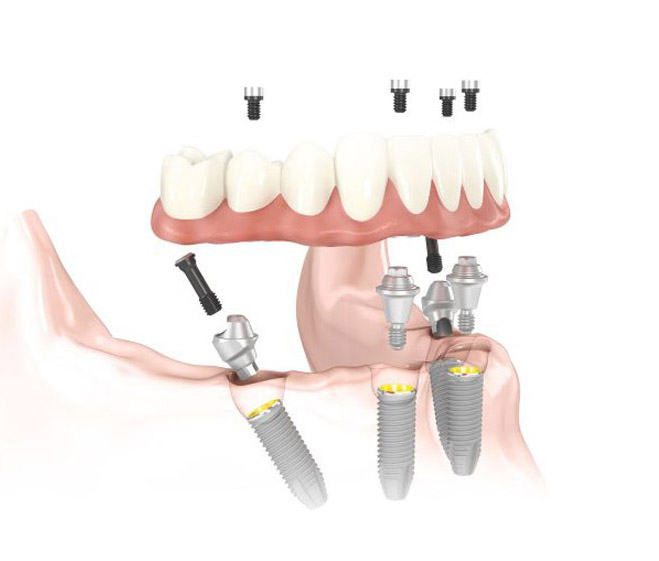

Full Mouth Dental Implants as Alternative to Dentures - Your certified provider of All on 4

Northview Dental is a certified provider of All on 4 Implant treatment, a prosthodontic procedure for patients with significant tooth loss, decay or bone loss to the point where a conventional dental implant is not possible. The All on 4 process involves surgically placing 4 implants in the jaw, on top of which a full tooth bridge is placed. This procedure can be completed in just one day!

BENEFITS OF ALL ON 4 INCLUDE:

- A great solution for patients with missing teeth or excessive bone loss

- Immediately improves your smile's function with new, natural-looking teeth

- Replaces dentures for life

- Improves oral health and hygiene

- Restores youthful appearance

- Long-lasting results

- Easy maintenance